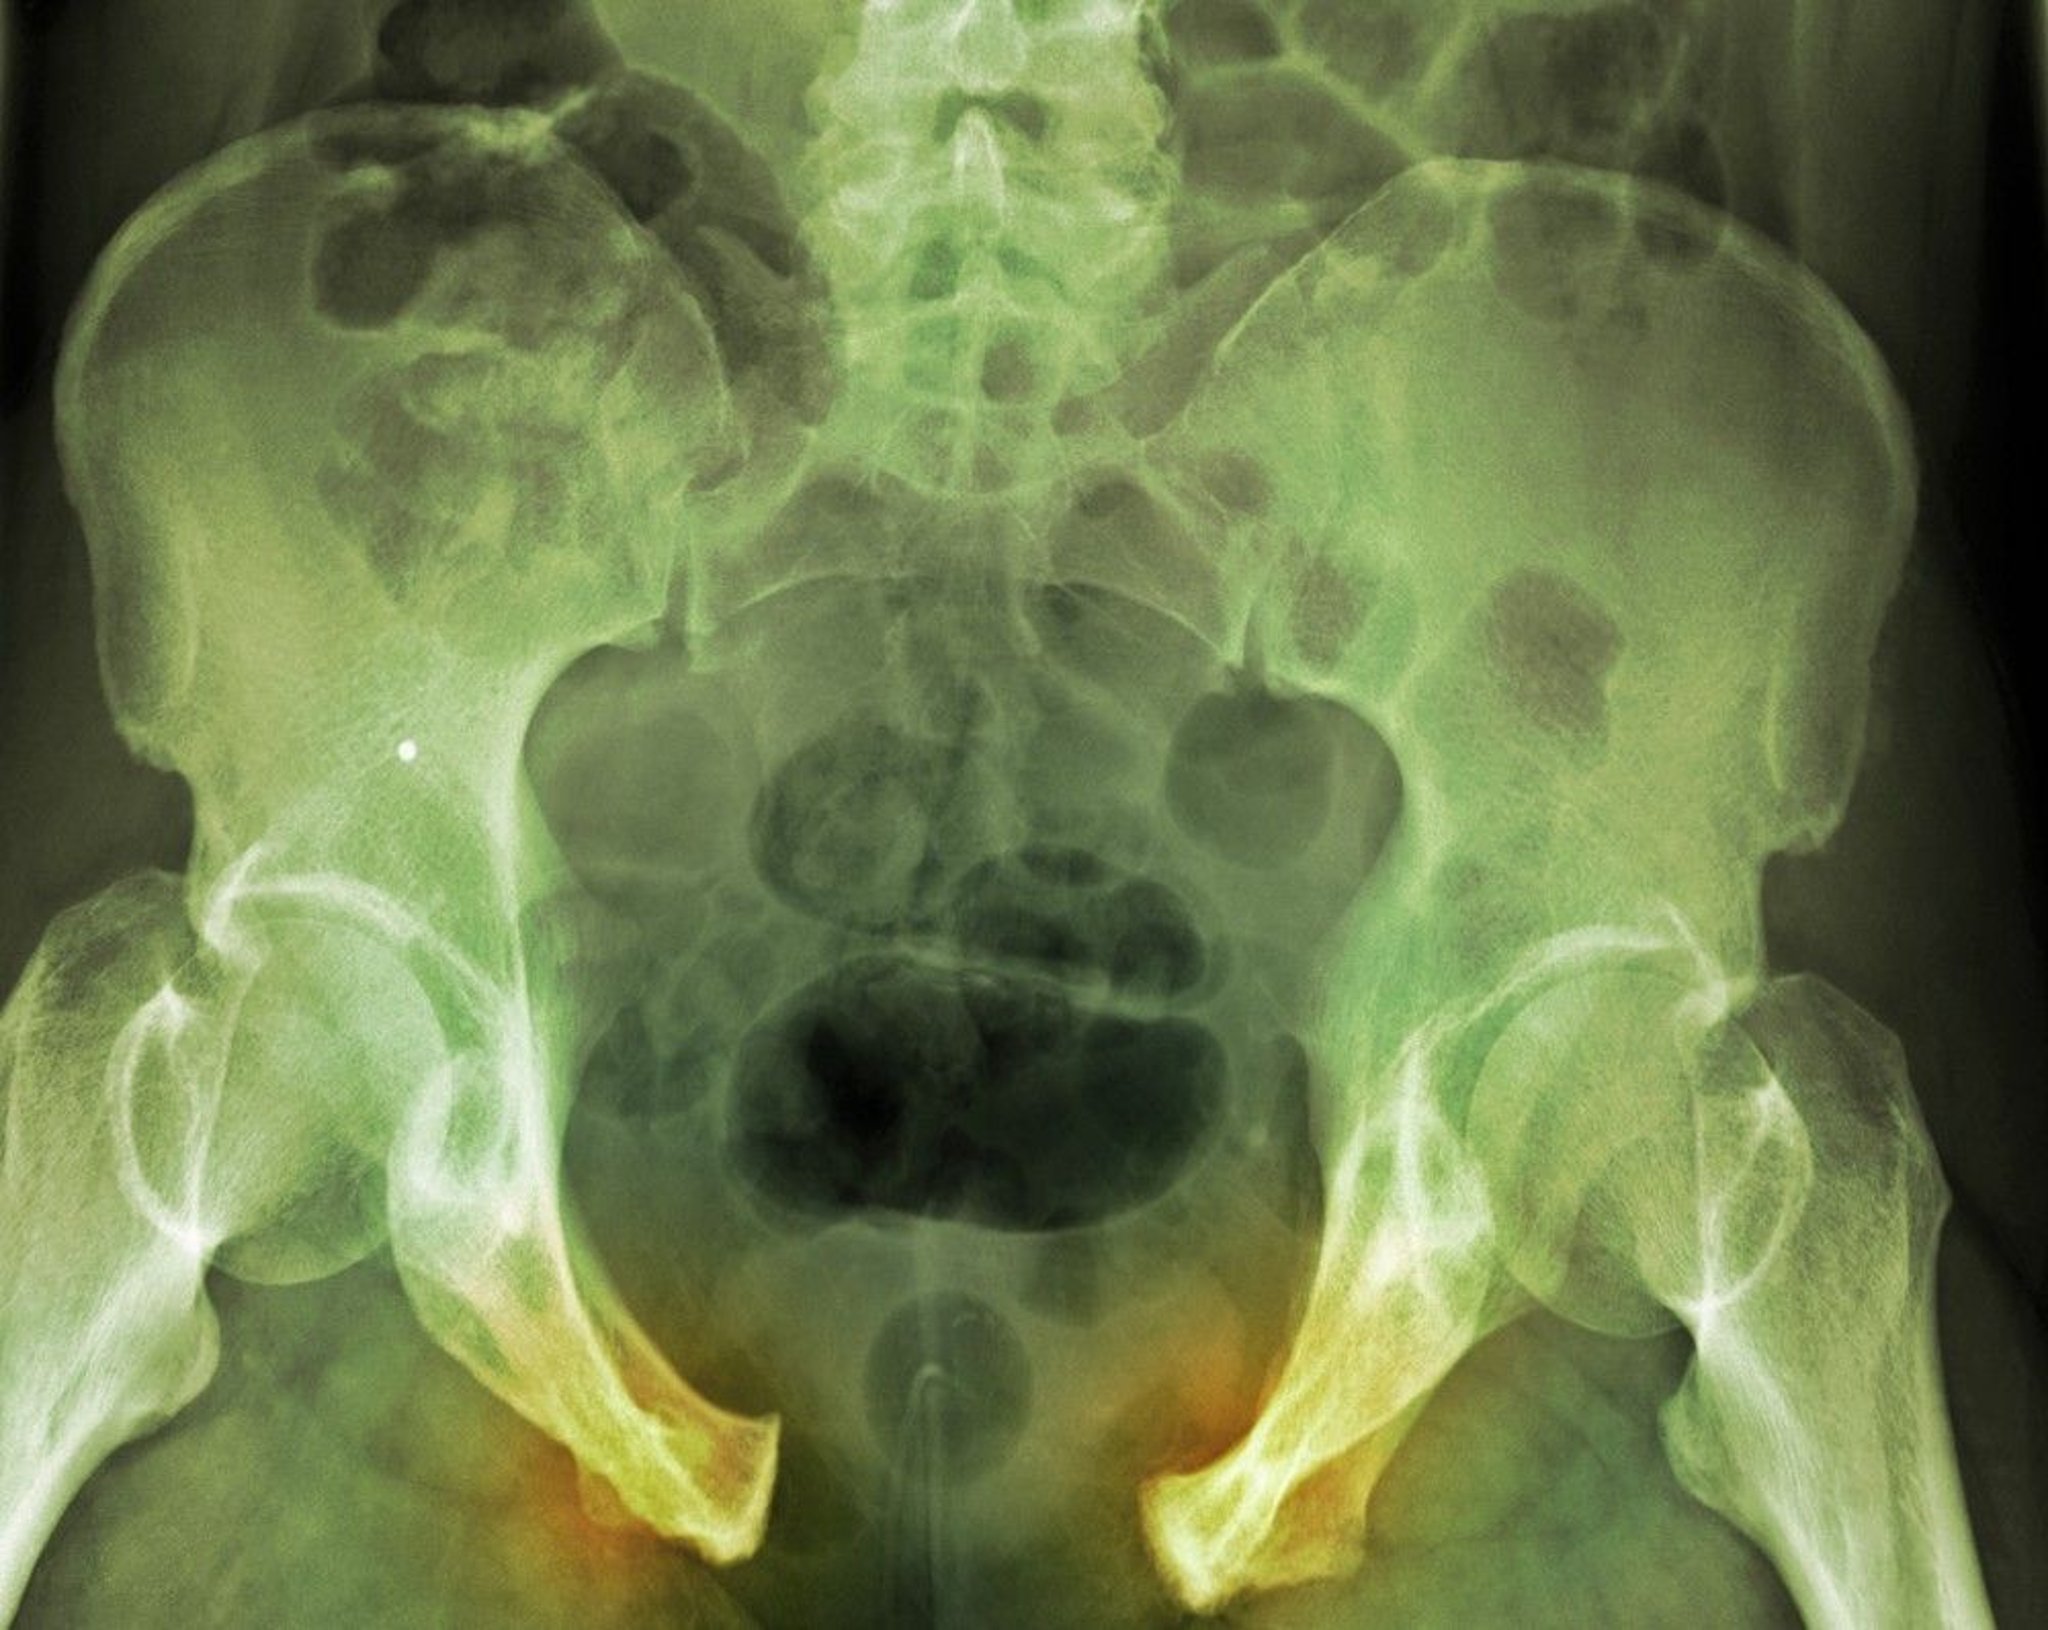

Pelvic Fracture

In this severe injury, disruption of the pelvic ring is clearly evident based on the widely separated pubic bone syndesmosis and the right-sided sacroiliac ligaments. Fracture lines are not as obvious.

DU CANE MEDICAL IMAGING LTD/SCIENCE PHOTO LIBRARY